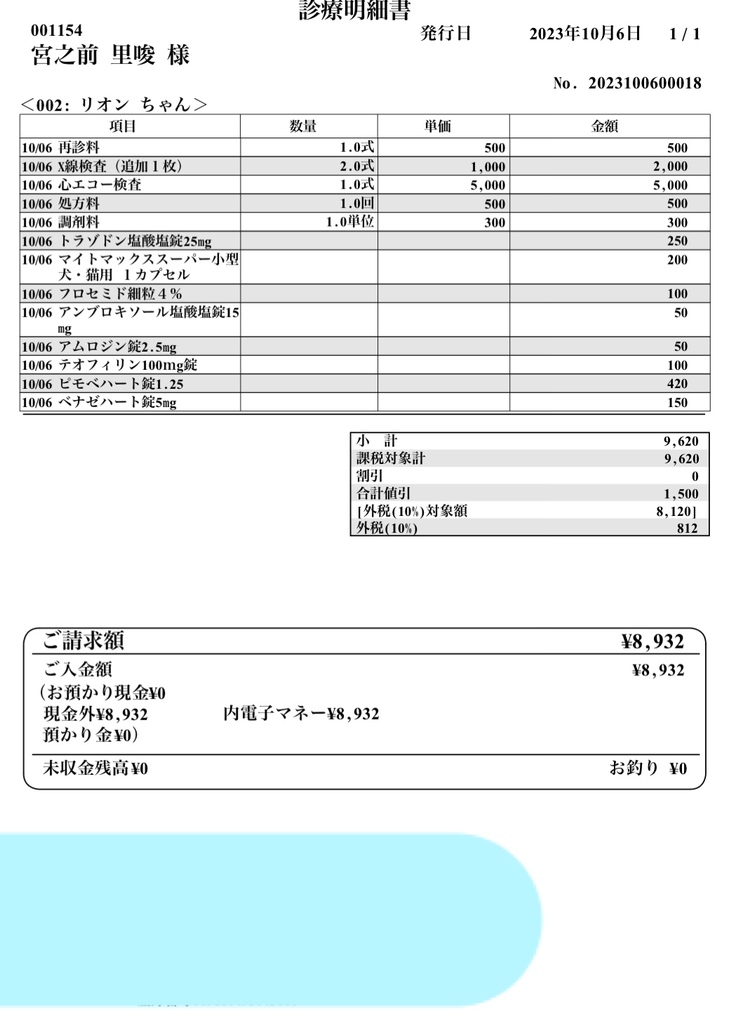

手術前の最後の検診

左が8/14 右が10/6

少し心臓が小さくなりました😌✨

今回出たお薬といつものサプリ💊